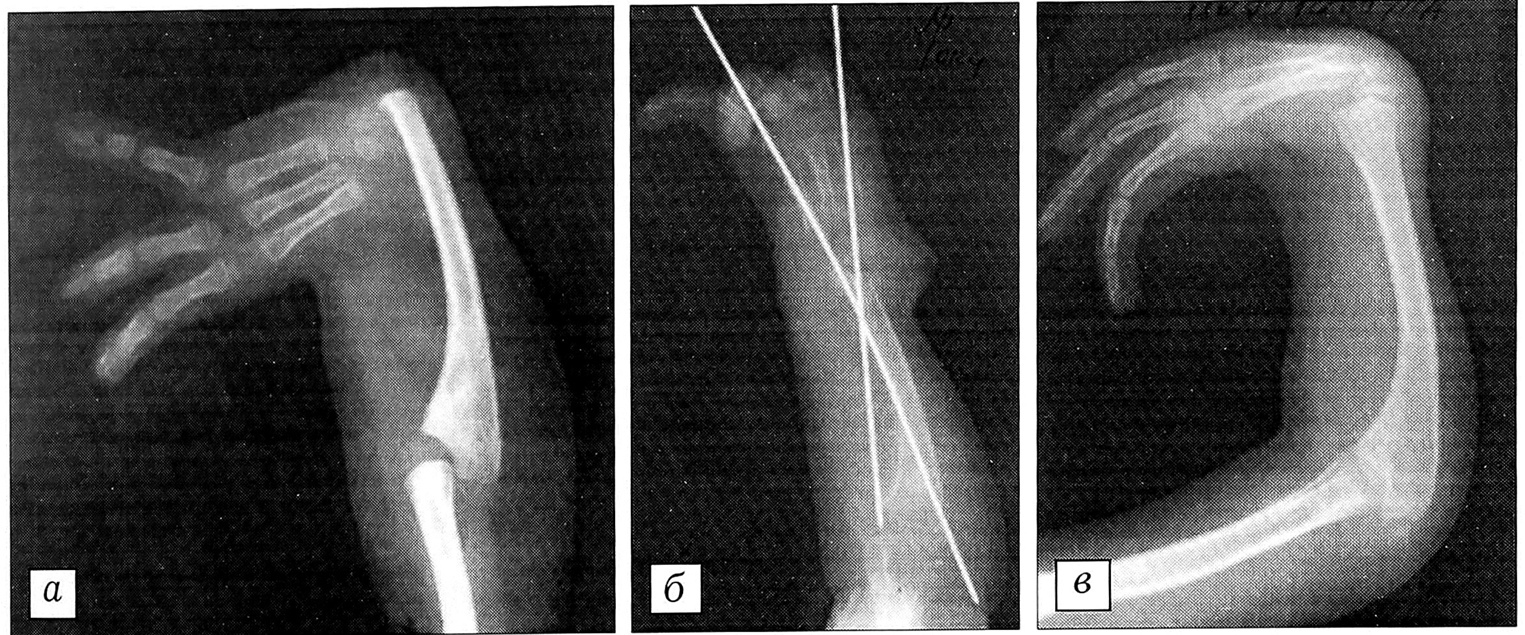

Наряду с перечисленными ошибками при лечении врожденной лучевой косорукости имели место и осложнения. Чаще всего (17 случаев) это была воспалительная реакция мягких тканей вокруг спиц после наложения дистракционного аппарата, что требовало более длительного консервативного лечения (локальная антибактериальная терапия или перепроведение спиц). В 7 случаях у больных старшего возраста, отпущенных домой на длительный срок с фиксационной спицей Киршнера и ведущих активный образ жизни, констатирован перелом центральной осевой спицы на уровне локтезапястного сочленения (рис. 3). Было произведено дополнительное оперативное вмешательство для удаления отломков спицы. Перечисленные выше осложнения не повлияли на окончательный благоприятный исход лечения.